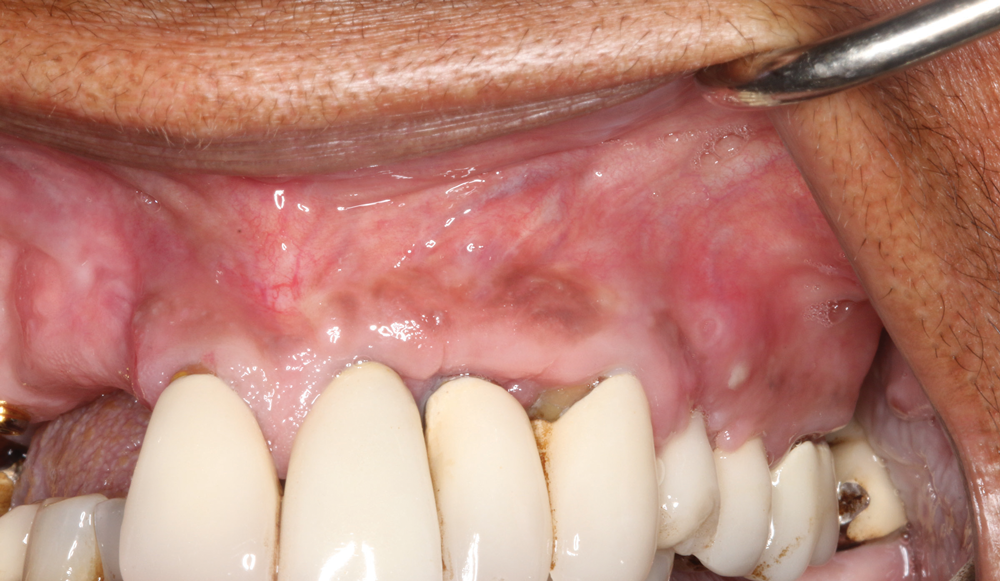

(13.) Follow-up 8-week postoperative photograph showing the site healing predictably.

Figure 13